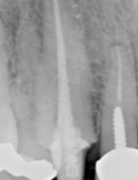

A 39-year-old female presented as a new patient for an implant consultation to replace missing tooth #30. A ULD CBCT (Figs. 1-2) was taken, and it was determined the patient was a candidate for implant placement.

Fig. 1

Fig. 2

A review of the scan revealed no pathology. The bone appeared to be dense with adequate width. The mandibular nerve was drawn, showing the nerve and the foramen were safely inferior to any position the implant would be placed.

Using Planmeca Romexis® software, the appropriate implant library was selected, and a Camlog iSY 4.4x13-mm implant was placed virtually, along with an abutment and library crown to help visualization of proper implant angulation.